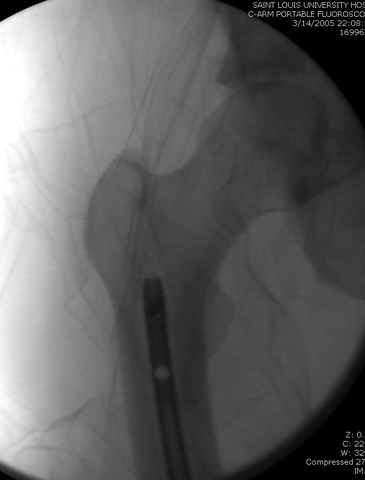

По поводу открытого перелома больной ургентно взят на ретроградное интрамедулярное штифтование, после рутинного дебрайдмента и фасциотомии на бедре и на голени.

интраоперационные